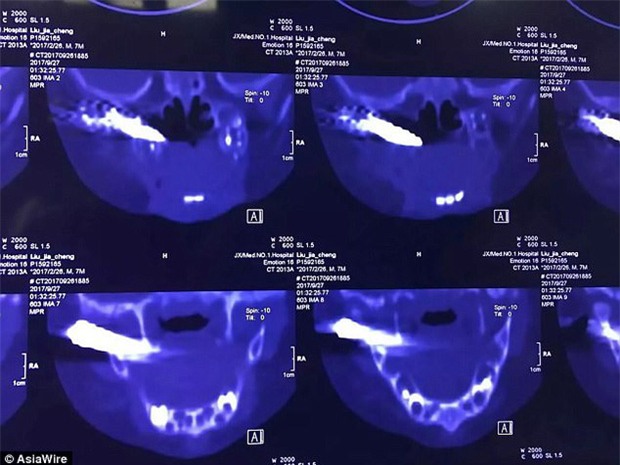

Sau khi chụp CT, bác sĩ phát hiện đầu mũi tên bằng kim loại dài 4cm lún sâu bên trong má nạn nhân.

Cháu bé đã được đưa tới bệnh viện Đại học Nanchang để cấp cứu. Sau khi chụp CT, bác sĩ phát hiện đầu mũi tên bằng kim loại dài 4 cm lún sâu bên trong má nạn nhân. Theo bác sĩ Yan Junfeng, mũi tên bắn trúng phần đầu ngay phía trước tai phải và gần khoang miệng.